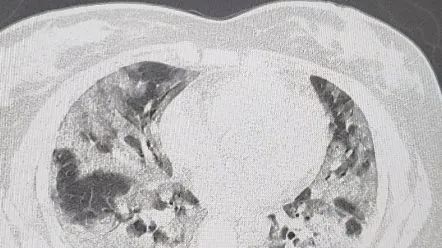

一位美国医生总结:为什么中国"大白肺”这么多?

不同于奥密克戎在其它国家的表现,也不同于上海疫情期间多数为无症状感染者的情况,这波中国疫情,不仅绝大多数感染者有明显症状,而且重症率也有明显升高,尤其表现在肺部感染上。

那么,为什么中国“大白肺这么多“呢?美国癌症医生张玉蛟教授在微博等社交媒体平台分享了他的观点,总结了三点: